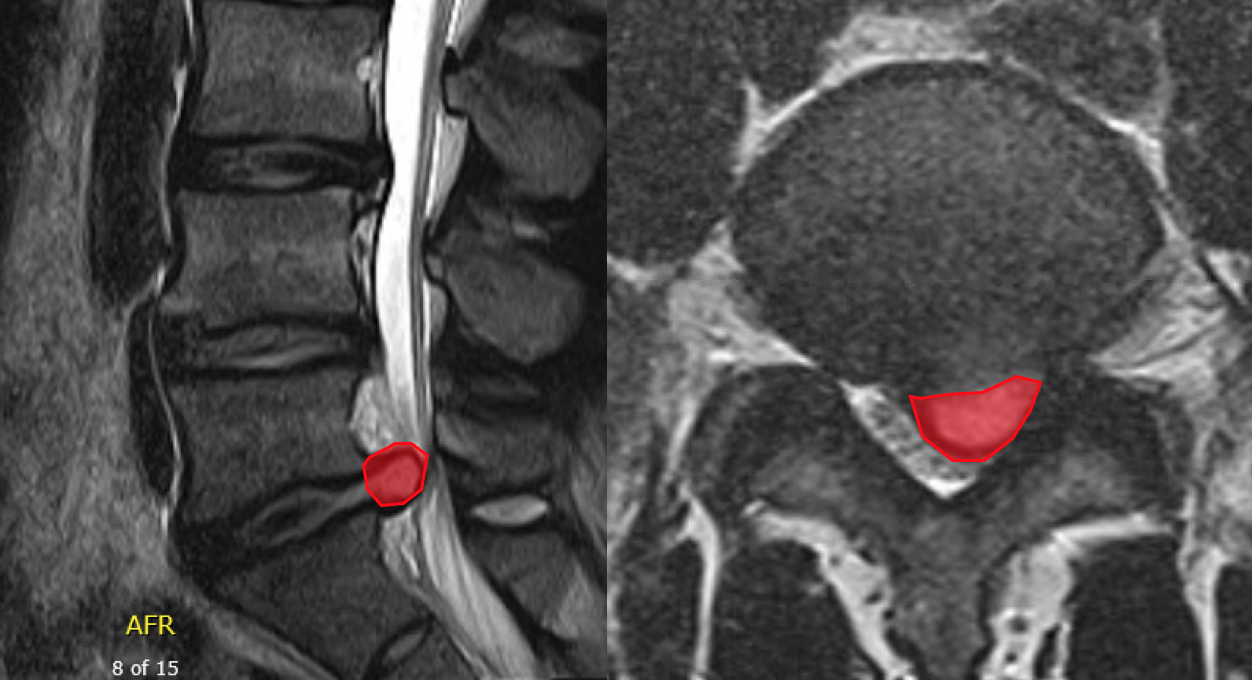

In this image the Red represents a Lumbar Disc Herniation or Herniated Nucleus Pulposis, a common cause of sciatica

During lumbar microdiscectomy surgery the red herniated disc material is removed, but this often leaves a large defect in the fibrous crust of the disc (annulus fibrosis). This is especially common in young, active patients.